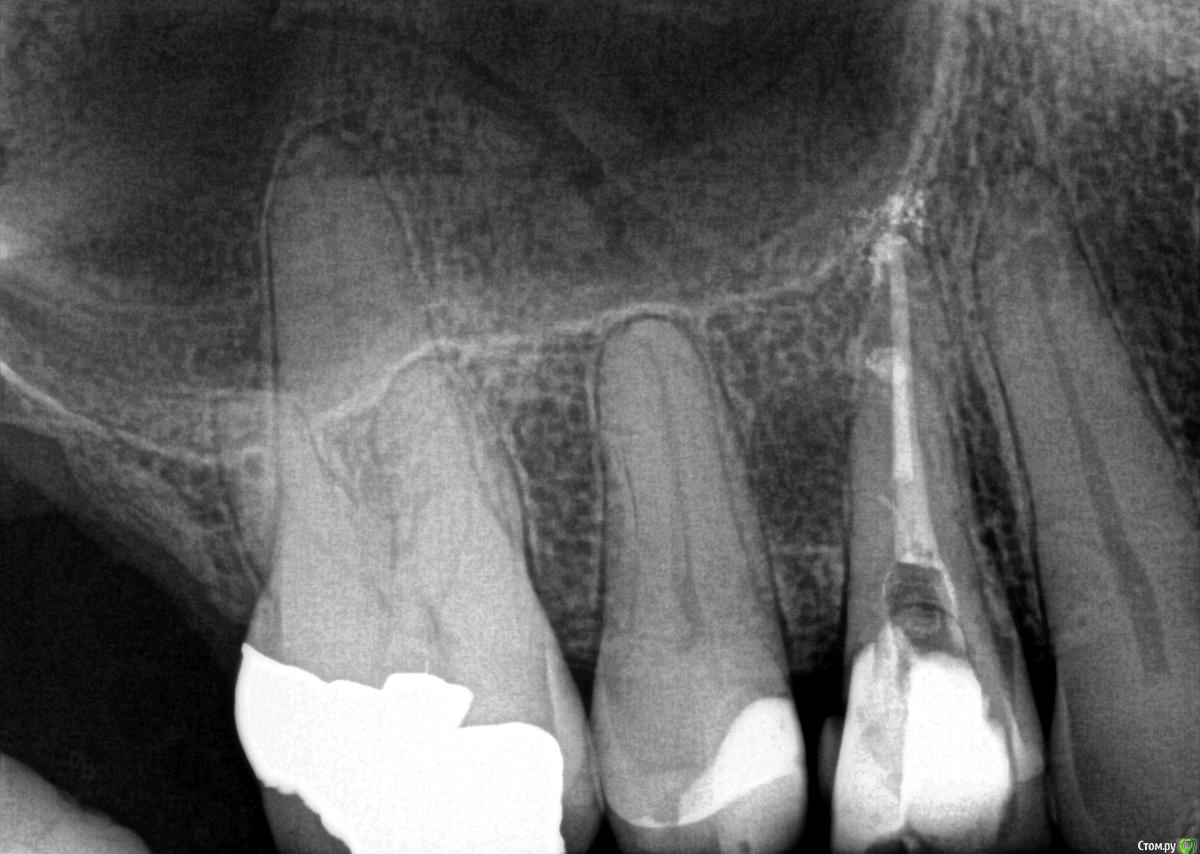

Rim3 Опубликовано 1 декабря, 2015 Поделиться Опубликовано 1 декабря, 2015 Уважаемые стоматологи, помогити пожалуйста! Во время пломбировки каналов верхнего бокового зуба с правой стороны у меня возникла резкая боль в районе синуса. Боль ушла через 3 -5 минут и врач настоял на продолжении лечения. Далее у меня опухла вся щека и появились синяки под глазами и щекой. Мне назначили стероиды и антибиотики. Как я позже поняла это было выведение гипохлорита натрия за пределы корня и травма. Теперь опухоль спала и синяки прошли. Я еще очущаю дискомфорт и некую болезненность в этой области.У меня теперь возник вопрос по поводу качества проведенного лечения каналов. Я собиралась закрыть зуб коронкой, но теперь сомневаюсь. Как вы считаете глядя на снимки, качественно ли запломбированы каналы? Что если не только гипохлотит натрия, но и гутаперча вышла за пределы корня. Возможны ли осложнения в будущем и операция по удалению лишнего материала? Ссылка на комментарий